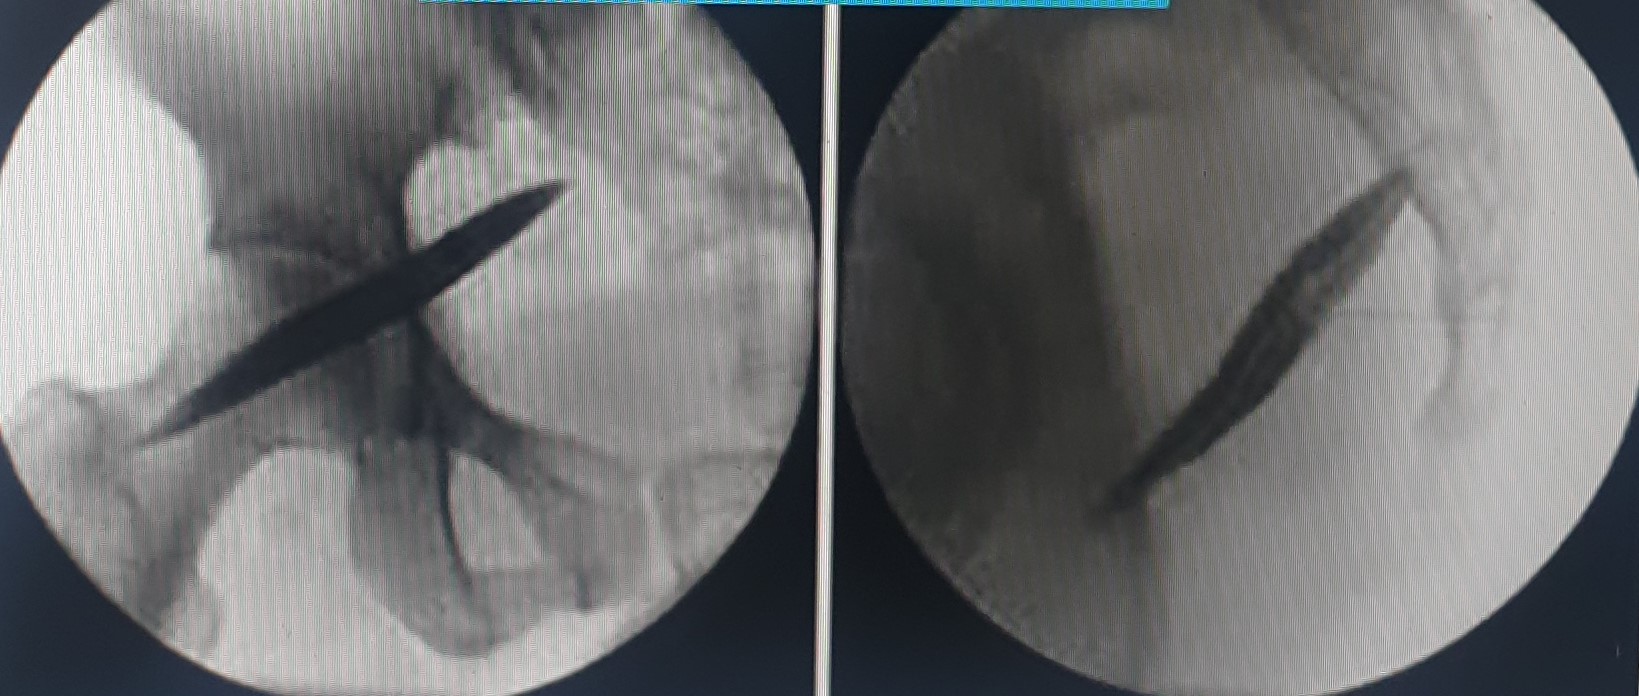

- Κρυοπηξία ή θερμοπηξία γαγγλίου Impar, για την αντιμετώπιση της κοκκυγοδυνίας

- Κατάλυση των ζυγοαποφυσιακών αρθρώσεων της κατώτερης ΟΜΣΣ και της ιερολαγονίου άρθρωσης με χρήση ραδιοσυχνοτήτων ή κρυοαναλγησίας